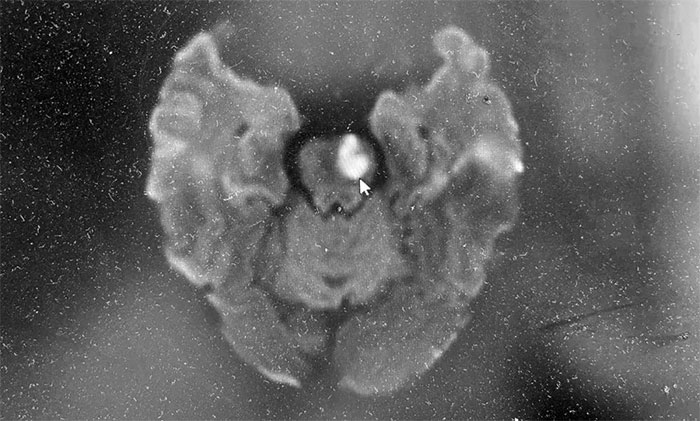

經(jīng)頭顱MRI檢查發(fā)現(xiàn),患者腦干及雙側(cè)基底節(jié)區(qū)多發(fā)點(diǎn)狀及小斑片狀異常信號(hào)。腦干新發(fā)梗塞,偏急性期,進(jìn)一步定位提示腦穿通動(dòng)脈閉塞,考慮橋腦腹外側(cè)綜合征。

▲ 磁共振檢查示:腦干新發(fā)梗塞,偏急性期